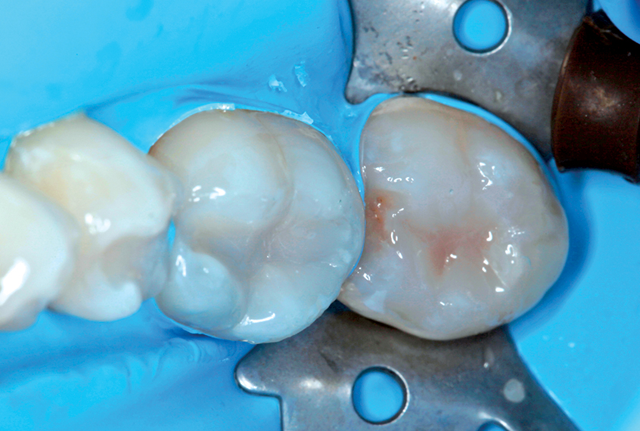

The same procedure was followed for the remaining eight restorations. Figure 7 shows several posterior teeth prepared for restoration and enamel etched with Select HV (BISCO) for 20 seconds (Fig. 8). Figure 9 shows the final restorations.

Fig. 7 Amalgam and decay are removed and tooth is prepared with ACTIVA BioACTIVE-RESTORATIVE. Fig. 8: Enamel etched for 20 seconds with Select HV

I chose ACTIVA BioACTIVE because the material releases and recharges fluoride, calcium and phosphate ions, and contains a rubberized component that resists fracture and chipping. ACTIVA BioACTIVE participates in an ionic exchange that is pH sensitive and supersaturates the saliva and pellicle during low pH cycles. As the pH rises, these minerals are available to form a layer of apatite on the tooth surface, supporting the natural mineralization process.

Fig. 9: Final restoration

The patient was pleased with the esthetics and impressed that all nine restorations were placed in a single appointment. She had been concerned about the possibility of infection resulting from untreated dental caries and wanted to complete the restorations before starting radiation therapy.